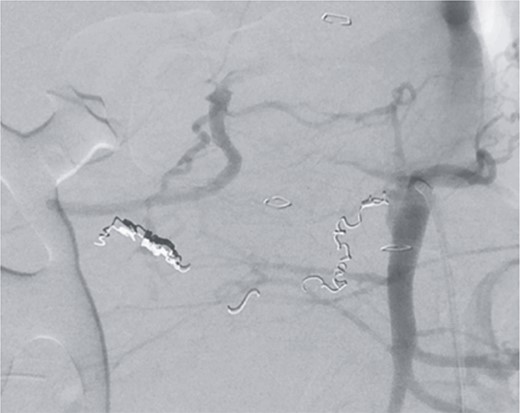

Postoperatively, the patient achieved hemodynamic stabilization in the intensive care unit. On the sixth postoperative day, there was a recurrence of circulatory collapse in addition to relevant bloody discharge through the drains. CT imaging once again revealed an active bleeding of the pancreaticoduodenal artery, which was successfully treated interventionally using coiling (Figs 2 and 3).

Angiography revealing the aneurysm of the pancreaticoduodenal arcade.

Postinterventional angiography, showing the aneurysm of the pancreaticoduodenal arcade, after interventional coiling.